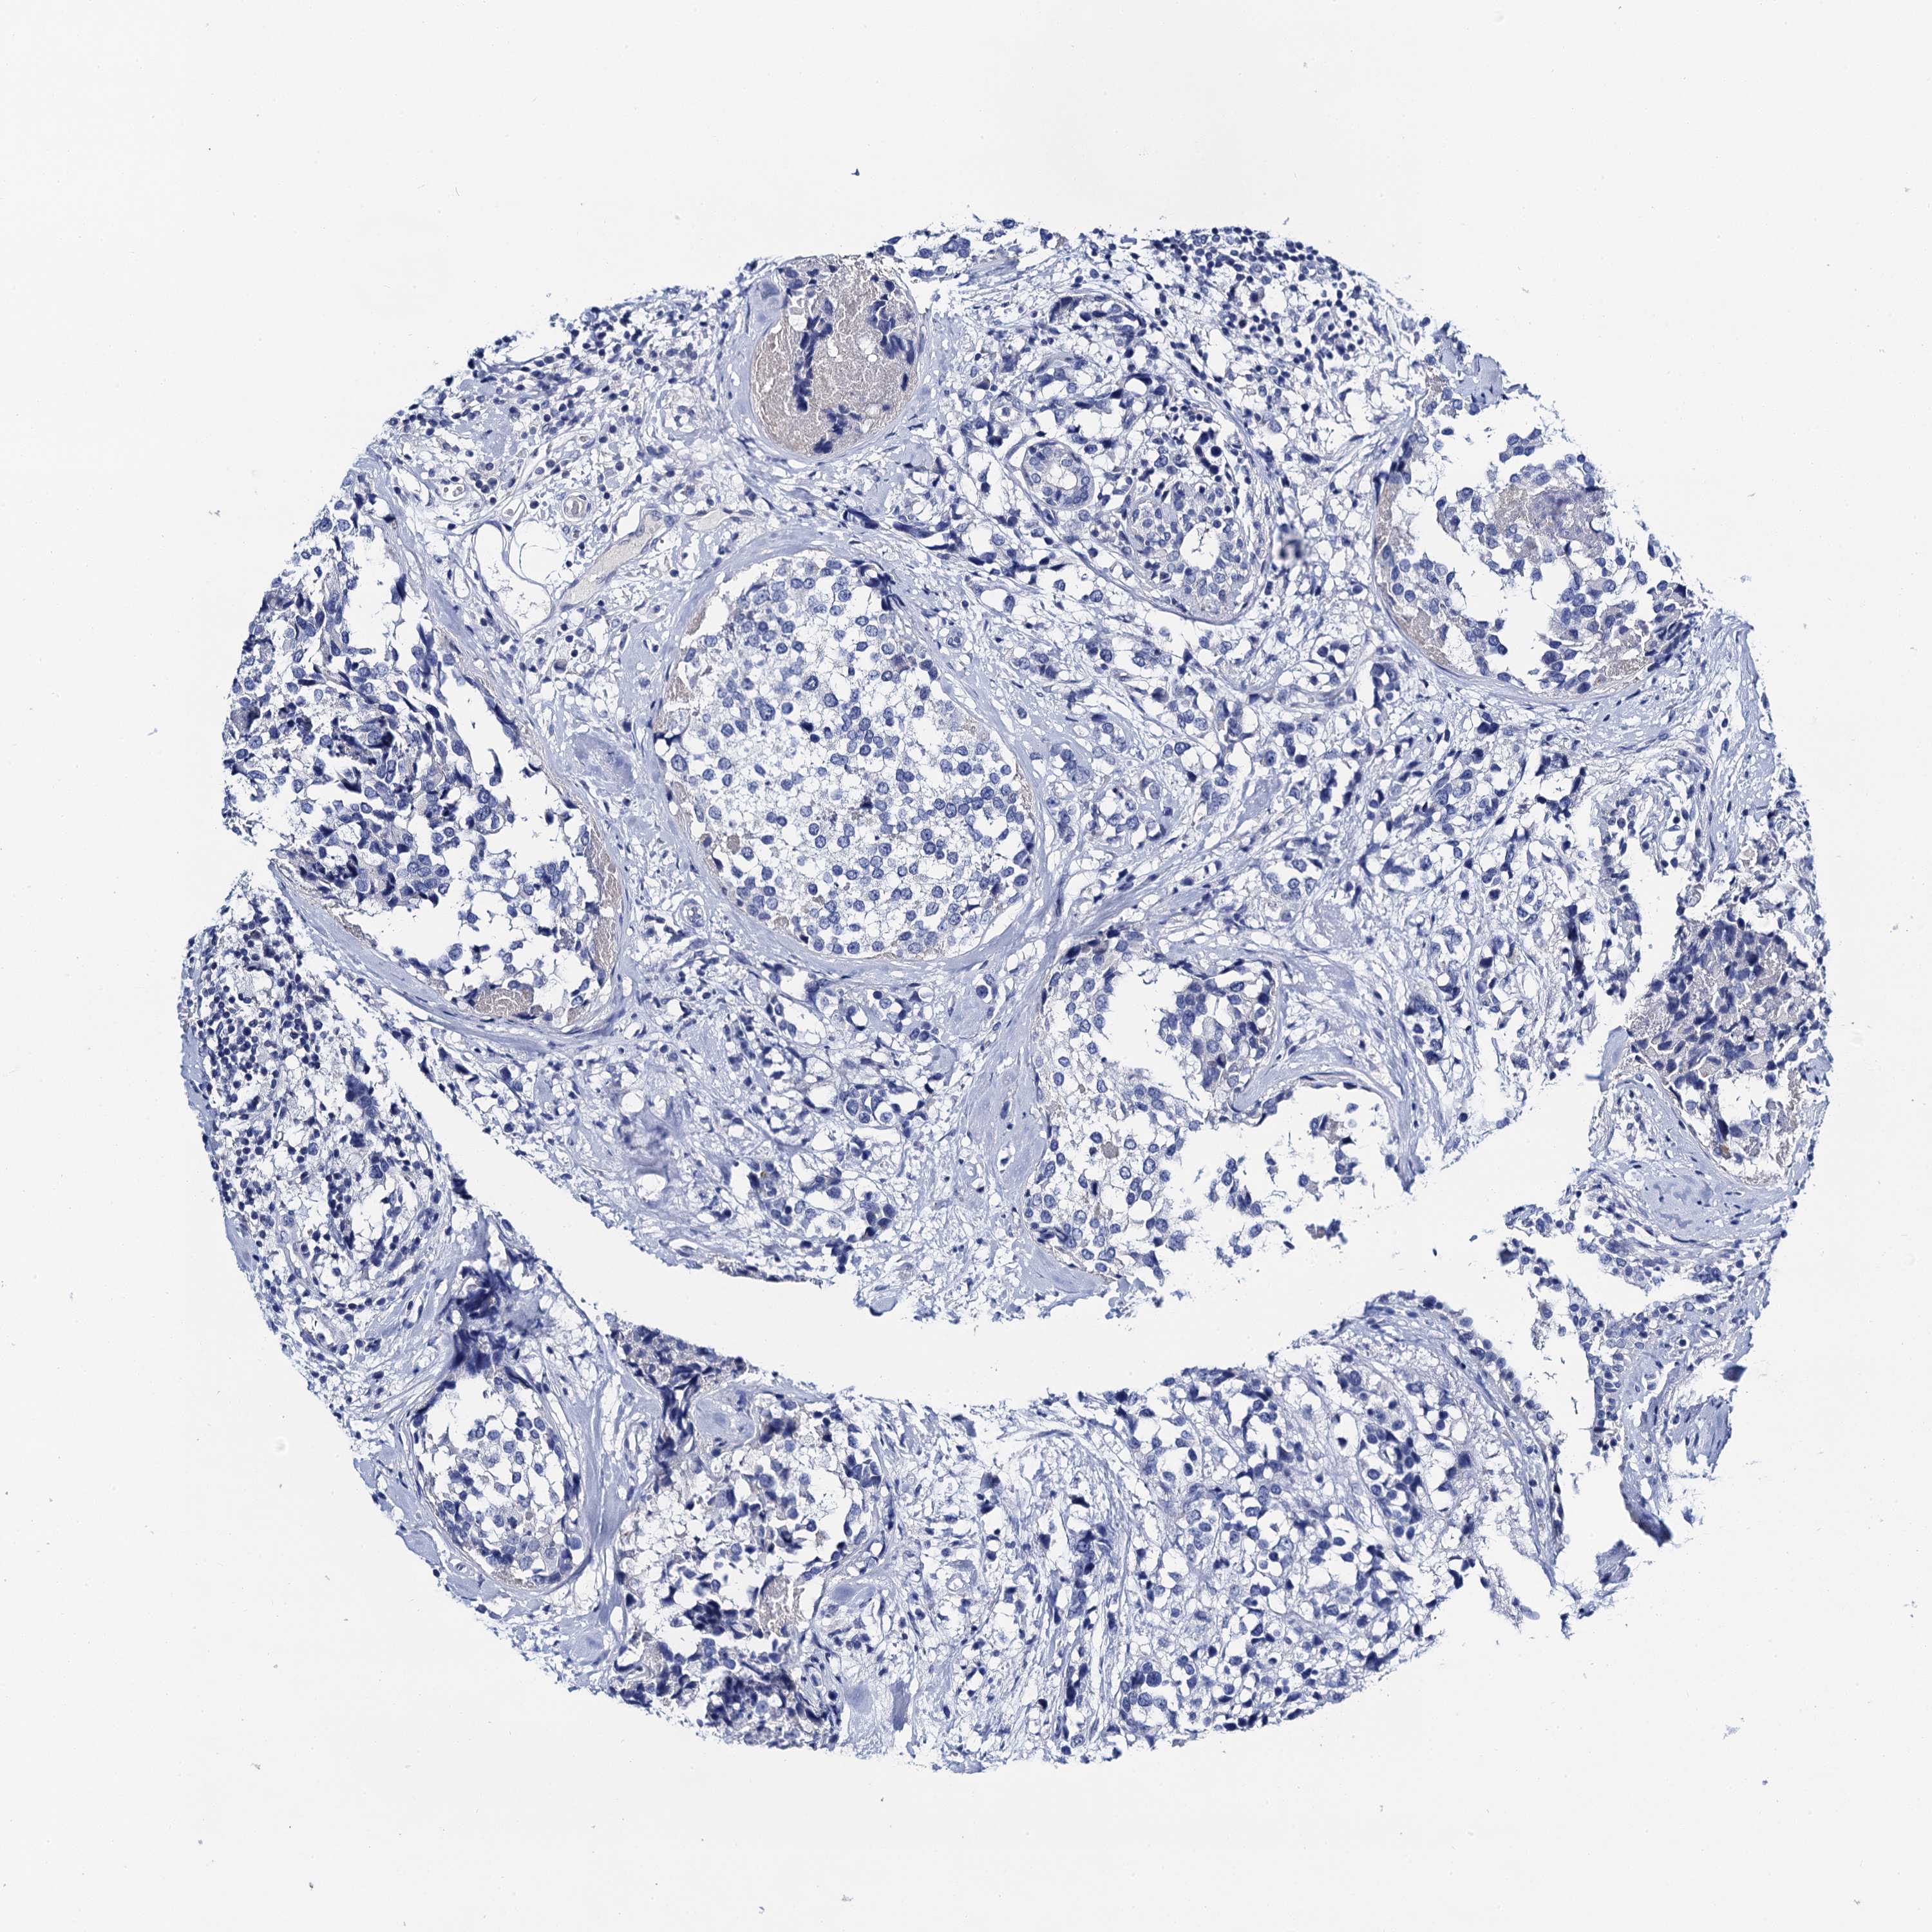

BRCA TCGA BRCA VALIDATION PROTEIN EXPRESSION